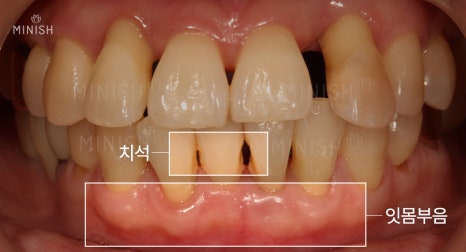

강정호 원장은 안성엄마의 치아 개선뿐 아니라 안성딸의 치아 건강을 위해서도 나섰는데요. 지난 번 꽃게엄마딸 기억하시나요? 노래를 하는데 치아틈때문에 발음이 새어 노래 할 때 불편감을 호소했었죠. 안성딸도 판소리를 하는데 치명적인 치아틈이 있었으며, 잇몸부음 등 문제를 보였습니다. 자세한 상태 확인해볼까요?

판소리하는 안성딸의 치아 문제는?

안성딸이 처음 치과를 방문했을 때 치아가 삐뚤고, 턱이 아프다고 했습니다.

상담과 진료를 진행해 보니, 턱통증의 원인은 수면중 이갈이나 이 꽉 무는 습관 등이 작용한 것으로 추정됐습니다. 그리고 잇몸염증, 잇몸부종, 치아틈 등 다양한 치아 문제가 발견됐죠.

잇몸염증, 잇몸부음은 세균에 의한 것이기 때문에 추후 안성엄마와 같이 풍치를 유발할 수 있는 상태였습니다. 그래서 잇몸치료로 잇몸 주변을 감싸고 있는 치석, 염증을 제거하였고, 구강관리에 좋은 환경 형성을 위해 잇몸절제술로 포켓 제거를 선 진행하였습니다. 그후 미니쉬로 치아틈을 폐쇄하고 전체적으로 깨끗한 치아를 만들어드렸습니다.